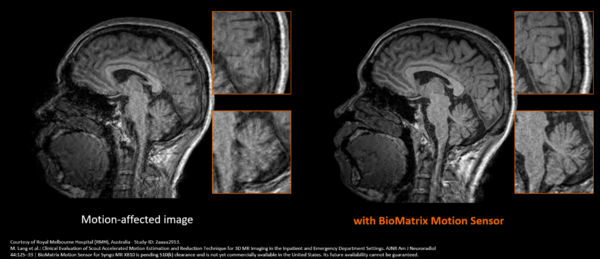

●BioMatrix Motion Sensorにより,被検者の動きによる画質劣化を抑制し,安定したMPRAGE撮像を実現(XB10より新たに搭載)

MPRAGE(Magnetization Prepared Rapid Gradient Echo)は,脳全体を高解像度の3D T1強調画像として取得できる撮像法で,認知症診断における脳萎縮評価や脳容積解析(Volumetry)に不可欠である一方,撮像時間が比較的長く,被検者のわずかな体動によって画質が劣化しやすいという課題があった。BioMatrix Motion Sensorは被検者の微細な動きをリアルタイムで検知し,MPRAGE撮像中の動き補正を自動で実行する。これにより,高齢者や安静保持が困難な被検者においても脳容積解析(Volumetry)に適した安定した3D画像を提供し,再撮像の低減と再現性の高い定量評価を可能にする。